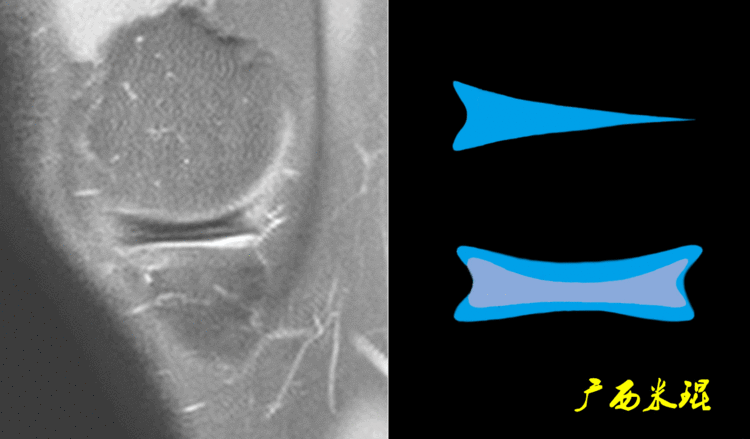

7、半月板后角内侧半月板周径较大,形似“C”形,后角宽,前角窄,后角宽度几乎是前角的2倍;外侧半月板周径小而面积大,形似“O”形,中部宽阔,前后角匀称,而且内外侧半月板后角为了适应内外侧胫骨髁和股骨髁而有着不完全相同的形态。

(2)隐窝隐窝是半月板后角与关节囊之间的正常凹陷,与体位等有关,可有可无,一般情况下积液越多隐窝越大,有上下之分,下面这张MR矢状位片见到的是上隐窝,紧贴半月板、光滑、不连通是其特点,也是鉴别要点。

下面这张MR矢状位片见到的是下隐窝,也紧贴半月板、光滑、不连通。